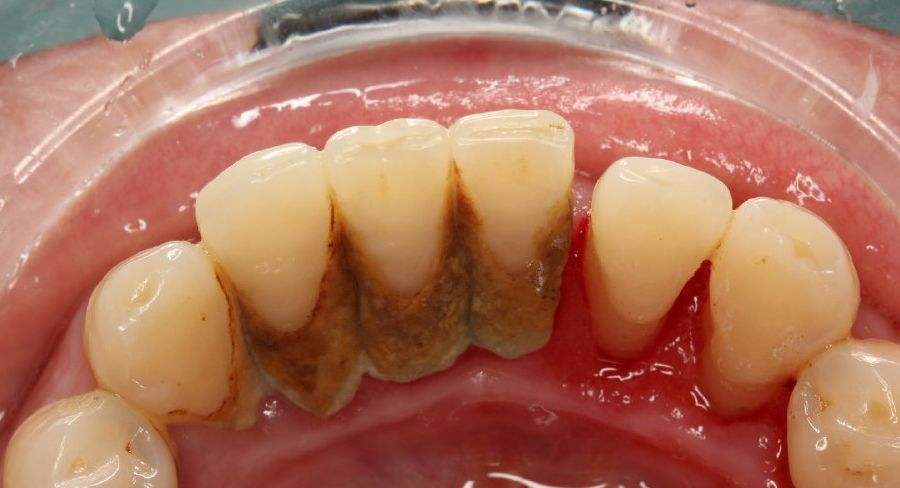

牙结石也是我们通常讲的牙石,主要成分是磷酸钙,一般是在下侧牙齿内侧积累呈现,我们可以观察到的是乳白色的软垢,随着时间推移会逐渐钙化,继而颜色变深,结石也会变硬,继而导致更为严重的牙周问题。

牙结石一旦成型,是很难通过刷牙来清除掉的,不仅会逐渐增多,甚至会越来越硬,形成肉眼可见的牙结石。

因为在牙齿表面有很多的牙结石,牙结石已经影响到了牙龈组织,细菌侵入牙龈,造成牙龈红肿易出血,容易出现牙龈炎。